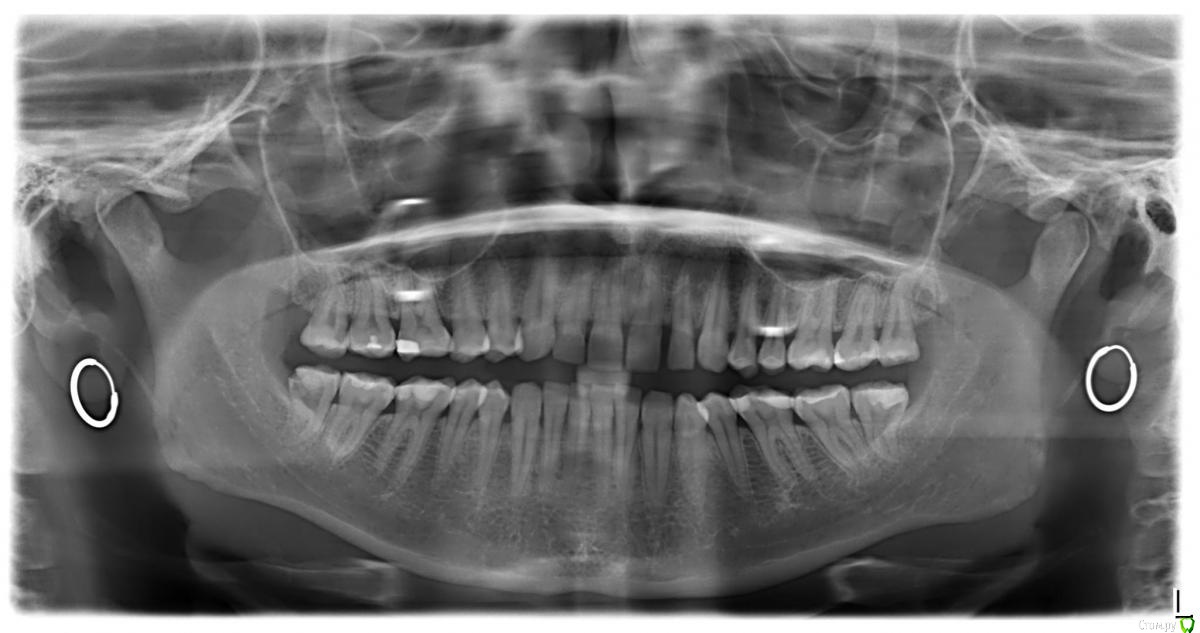

Mary5 Опубликовано 13 марта, 2020 Поделиться Опубликовано 13 марта, 2020 Здравствуйте!Помогите пожалуйста разобраться в ситуации с 6-й в верхнем правом ряду.В конце декабря поставили пломбу. Врач показалась не очень опытной, и приходилось после установки пломбу подтачивать, не прекращалась боль при нажатии на зуб, при смыкании. Сперва списывала всё на боль сразу после лечения, потом на избыточную нагрузку из-за плохо подогнанной поверхности. Прошло уже 2,5 месяца, но боль не проходит, а лишь усилилась. Сделала снимок, и сегодня отсматривали его в той же клинике, но уже у другого врача. По мнению врача - всё ок! Но мне больно, зуб реагирует на холодное, горячее, и просто в состоянии покоя, боль только усилилась. Насколько я смогла понять сама по снимку - под пломбой есть какое-то затемнение, и это может быть вторичный кариес. Что делать в таком случае, если лечащий врач клиники, где пломба на гарантии - говорит что всё в порядке? Какие есть методы диагностики, которые я могу провести для уточнения ситуации в других клиниках? Что по данному снимку видно Вам? Может быть и правда всё в порядке - но в чем тогда может быть причина непроходящей столько времени боли???Спасибо! Снимок прикрепляю. Ссылка на комментарий

red_butler Опубликовано 15 марта, 2020 Поделиться Опубликовано 15 марта, 2020 да, боль ощущается в районе этой 6-ки, как будто в глубине. Нужно очно смотреть и провести термопробу хладагентом, при необходимости лечить 1.6 зуб, и зубы мудрости справа удаляйте Ссылка на комментарий

red_butler Опубликовано 15 марта, 2020 Поделиться Опубликовано 15 марта, 2020 А что значит "1.6"? Это опечатка, или какое-то обозначение правой верхней шестерки? да, это обозначение первого моляра на верхней челюсти справа, По поводу шестерки - а может быть боль от плохо подогнанной пломбы? нет, судя по снимку рог пульпы близко к полости, нужно исключить пульпит Ссылка на комментарий

Mary5 Опубликовано 15 марта, 2020 Автор Поделиться Опубликовано 15 марта, 2020 (изменено) Понятно. А как его диагностировать? Врач клиники, где делали, как уже писала, говорит, что да мол, близко, но это снимок так показывает - наложение проекций, на самом деле там ещё "километр". На мой вопрос: как более точно этот "километр" увидеть - может стоит делать кт - говорит, что ни к чему. Но зуб-то болит. Почему-то. И почему она отказывается проводить диагностику причин - мне не понятно. Искать другую клинику, делать там кт и там же в случае чего лечить, не смотря на то, что в первом месте ещё гарантия? Изменено 15 марта, 2020 пользователем Mary5 Ссылка на комментарий